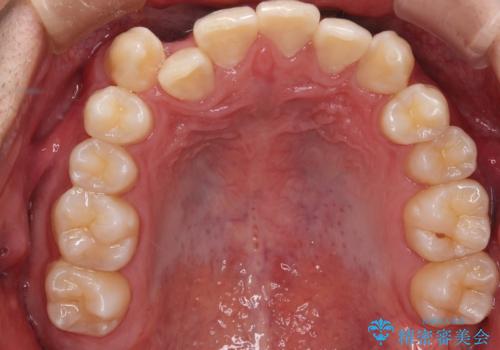

その点を考慮して、リンガルアーチを用いて奥歯を遠心移動し、前歯にIPR(歯と歯の間を削る処置)を行うことでスペースを作って歯並びを整えていく計画を立てました。

リンガルアーチを用いて奥歯を遠心移動し、前歯にIPR(歯と歯の間を削る処置)を行うことでスペースを作って歯並びを整えていく計画を立てました。

心配していた歯肉退縮も起こらず、前歯の噛み合わせと歯並びが綺麗に改善されました。